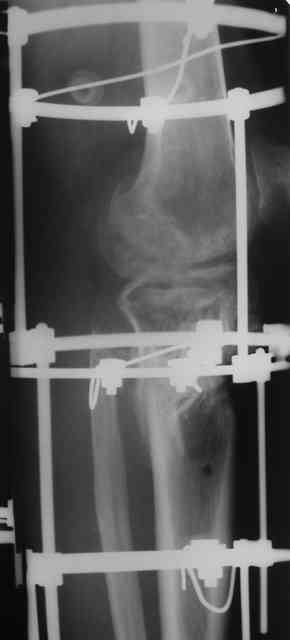

Р-граммы и фото за 4.05.2007 - 7-е сутки после операции.

Ход операции - линейным разрезом по передней поверхности голени обнажена зона ложного сустава большеберцовой кости. От кости отсепарованы медиально м/ткани. Из зоны ложного сустава убраны рубцовые ткани, мобилизован дистальный отломок. По передней поверхности удалены два осколка, связанных грануляциями. Произведено удаление грануляционной ткани из проксимального отломка (на вид сине-серого цвета), "чистого" гноя не было. Затем произведено наложение аппарата и репозиция отломков. По передне-медиальной поверхности образовался дефект до 4х2х2 см + полость в проксимальном отломке. Удаленные осколки очищены от грануляций, уложены в место дефекта, зажаты между отломками. После иссечения раны по передней поверхности, находящейся рядом с операционной раной, последняя ушита с большим натяжением.

Перелом мыщелка сросся. Проксимальный отломок очень порозный.